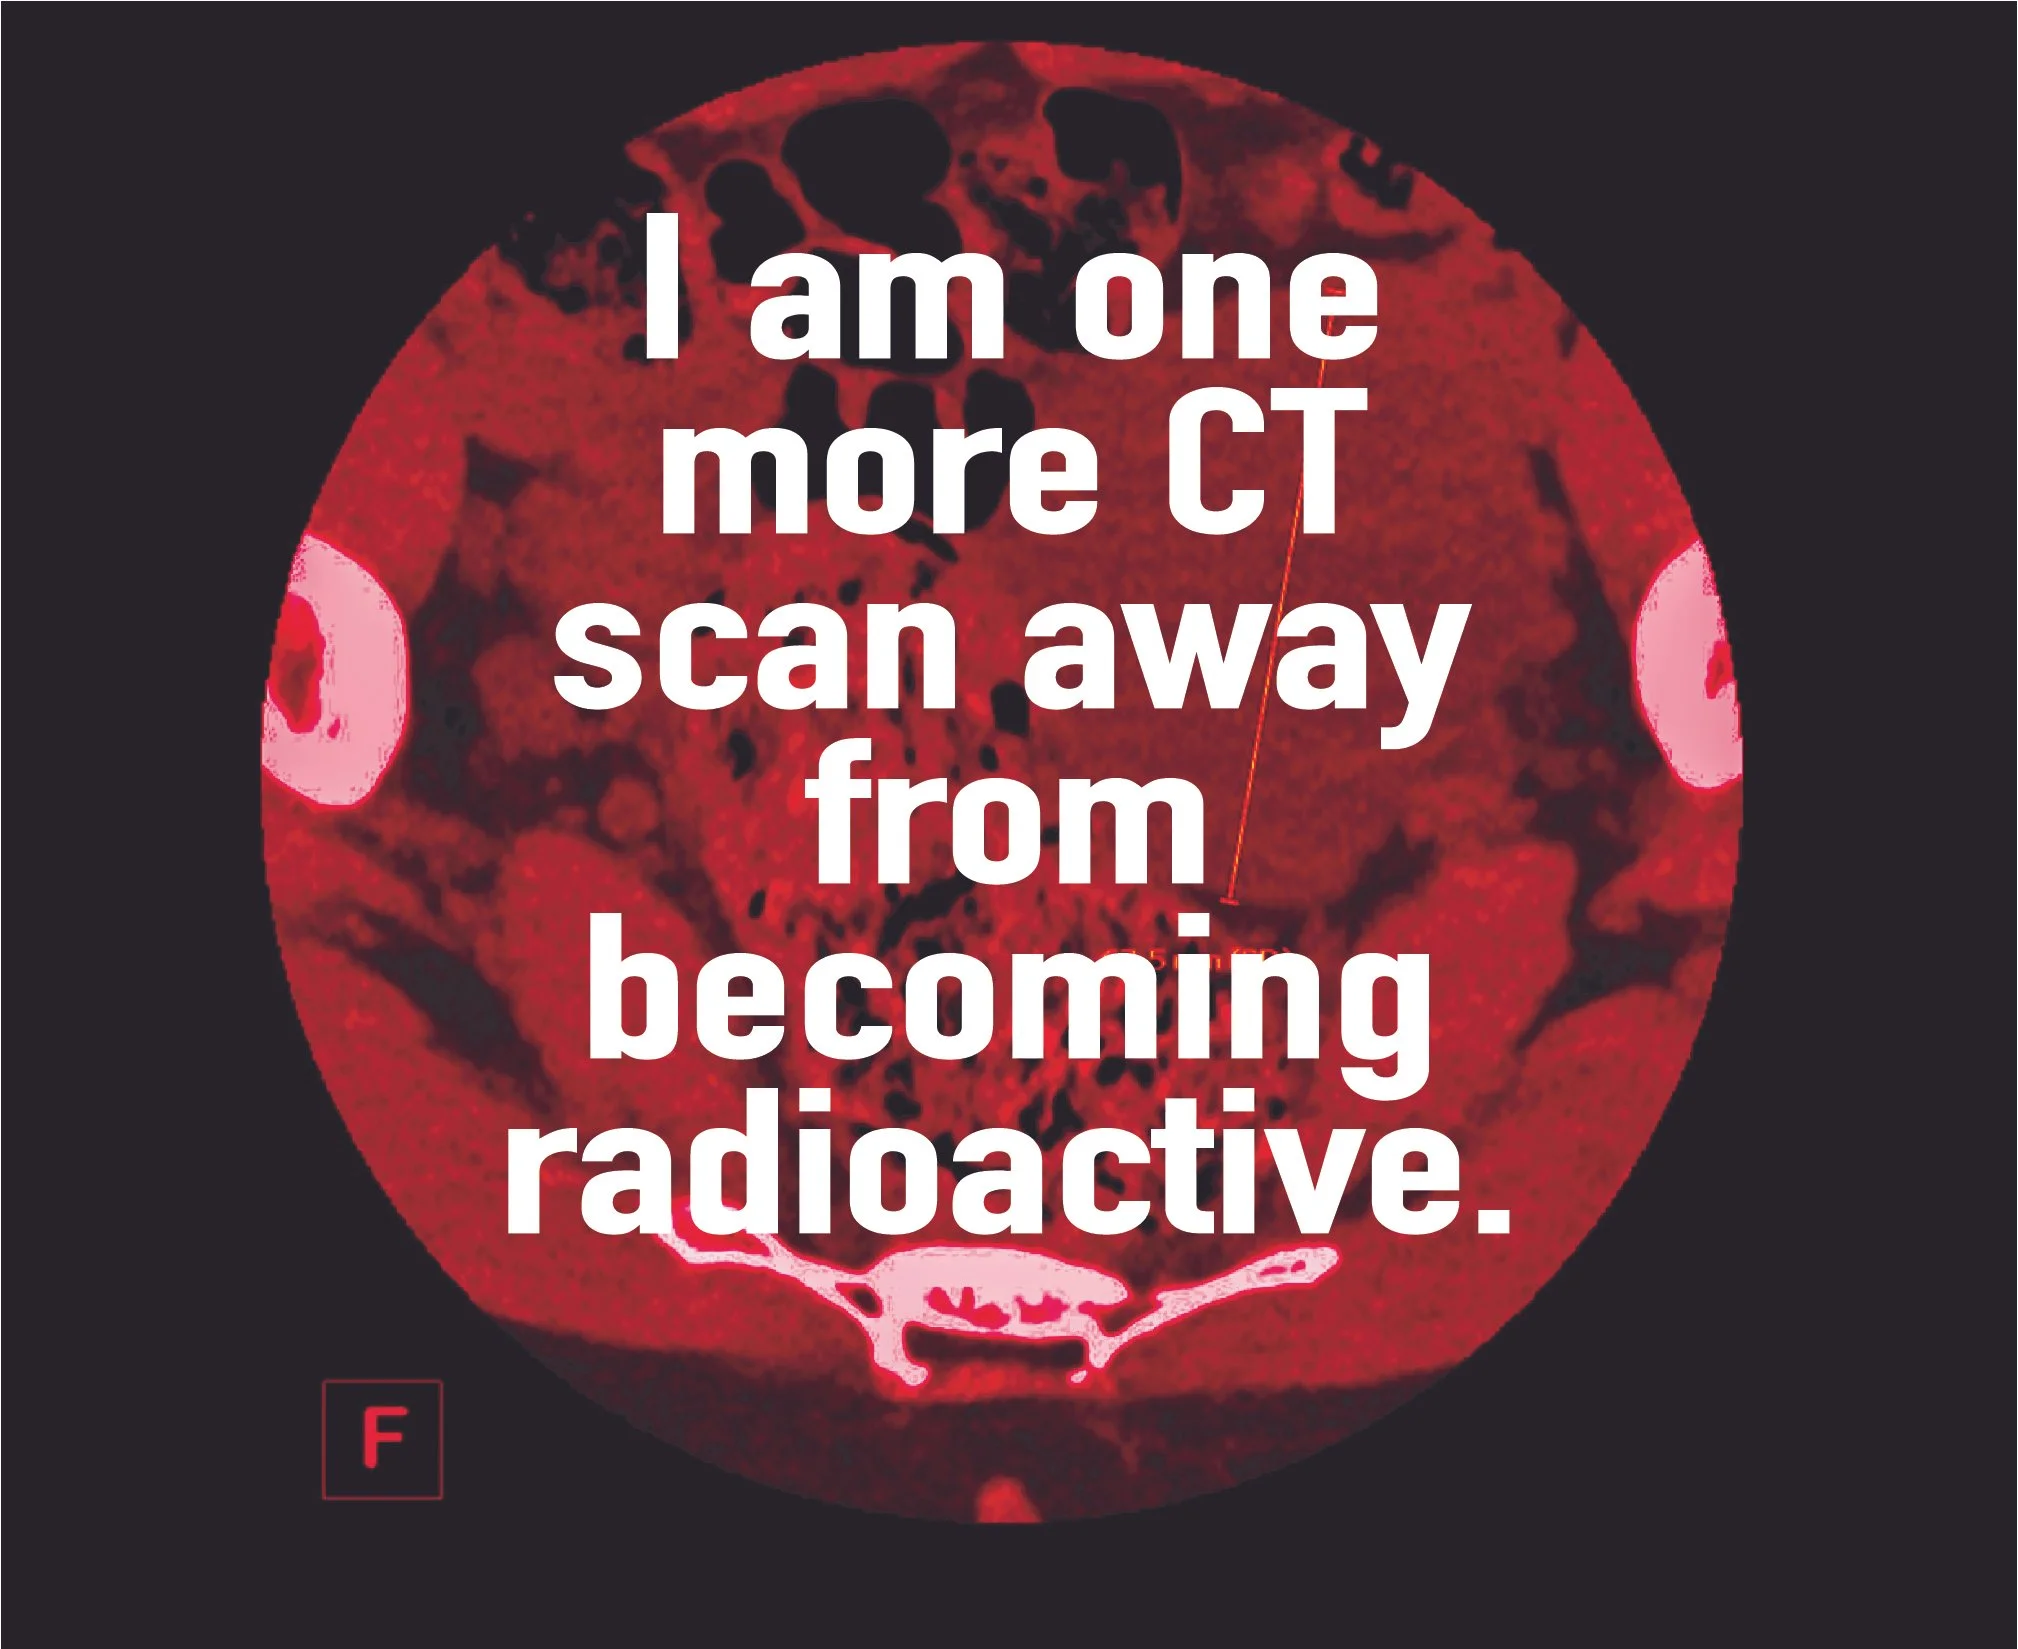

Confessions of a Bad-Backed Young Masc